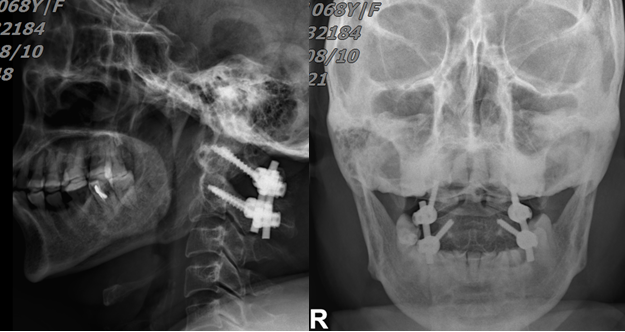

經(jīng)過充分的術(shù)前溝通和準(zhǔn)備,8月7日,陳志伸主任醫(yī)師、王慶敏副主任醫(yī)師及其手術(shù)團(tuán)隊(duì)依靠精湛的技術(shù),歷時2小時,成功為患者實(shí)施了“頸后路寰樞椎釘棒內(nèi)固定+植骨融合術(shù)”。術(shù)后第1天患者可以在支具保護(hù)下坐起,術(shù)后3天可獨(dú)立下地行走!

圖三:術(shù)后復(fù)查:螺釘位置良好,骨折復(fù)位滿意